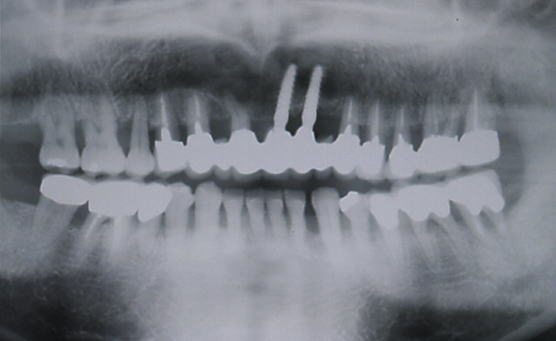

症例109